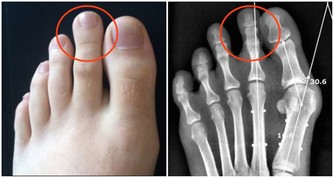

3、大魚大肉、愛喝酒吃太多蛋白類食物,會產生過多的尿酸和尿素氮等代謝廢物,加重腎臟負擔。

大量飲酒容易導致高尿酸血症,這些習慣可引起高血脂等代謝疾病,引發腎臟疾病。